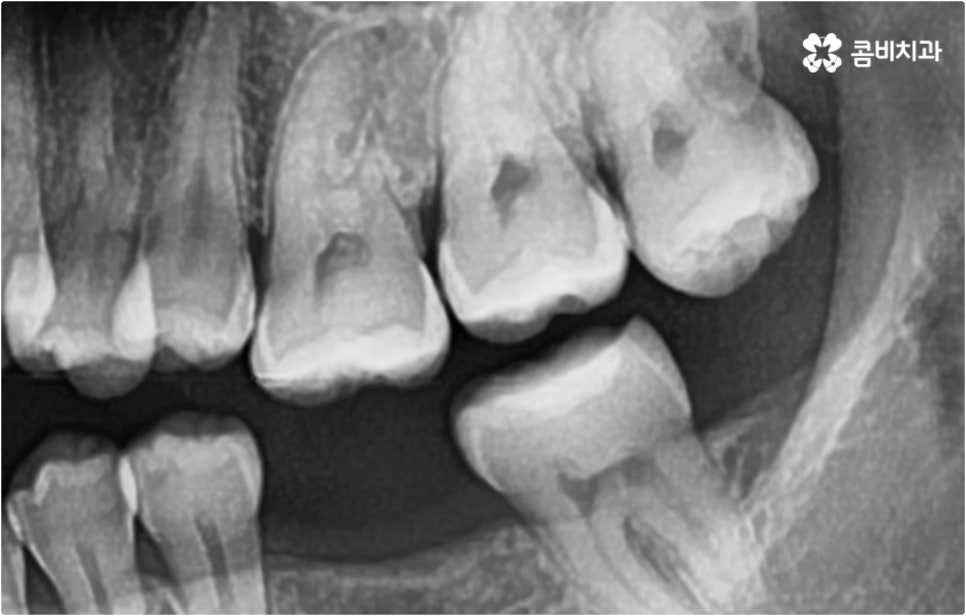

이때 현재 상황을 정밀하게 보여주는 3D CT, 미래 결과를 예측해서 보여주는 모르페우스와 같은 디지털 장비를 통해 전체 플랜을 자세하게 설명해 주고 중간 과정 역시 꼼꼼하게 브리핑해 주는 의료진과 함께 교정 치료를 진행한다면 조금은 길고 힘들게 느껴질 수 있는 전체 교정 과정에 보다 적극적이고 긍정적인 마음으로 임할 수 있을 거예요. 또한 앞서 말씀드린 것처럼 불편함을 줄여줄 수 있는 다양한 교정 장치와 방법 등이 있으니 가능한 선택지 내에서 자신의 상황에 최적화된 장치를 이용해 보시면 여러모로 도움을 받으실 수 있습니다.

이와 같이 치아설측교정 과 콤비교정은 브라켓을 치아 안쪽으로 붙여서 치료하는 방식이기 때문에 굉장히 고난도의 복잡한 교정 치료라고 할 수 있습니다. 교정에 대한 높은 이해도와 해부학적으로 뛰어난 노하우, 풍부한 경험을 통해 축적한 세심한 기술력을 갖추고 있는 의료진에게 치료를 맡기는 것이 중요하며 정밀 디지털 검진 장비를 통한 정확한 검사 결과를 바탕으로 무리하지 않게 진행하실 필요가 있어요. 또한 양치질을 할 때 음식물 제거가 쉽지 않으므로 환자분들 본인이 평상시 신경써서 닦아주시는 것은 물론 꼼꼼한 케어시스템을 통해 주기적으로 관리해 주는 치과에서 교정 치료 및 사후 유지 관리까지 철저하게 받아보시길 권유드리고 있습니다.